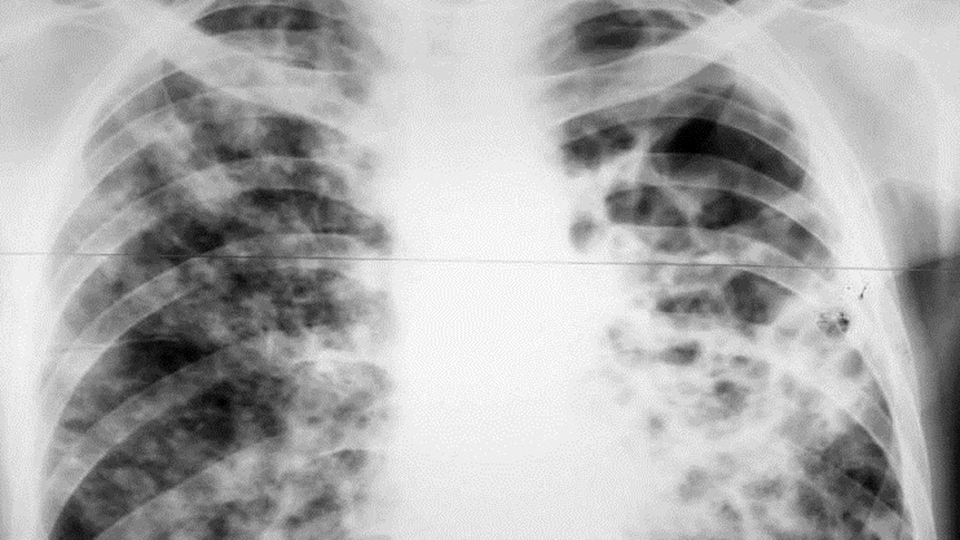

Жительница Дергачей, имея активную форму туберкулеза, пренебрегала рекомендациями врача. При неоднократных добровольных госпитализациях она покидала стационар спустя две недели.

Суд вынес решение о принудительной госпитализации в противотуберкулезный диспансер.

Получив исполнительный документ немедленного исполнения, судебные приставы Дергачевского района установили местонахождение гражданки и в средствах индивидуальной защиты доставили ее в областной противотуберкулезный диспансер.

Женщине предстоит пройти обследование и длительный курс лечения.